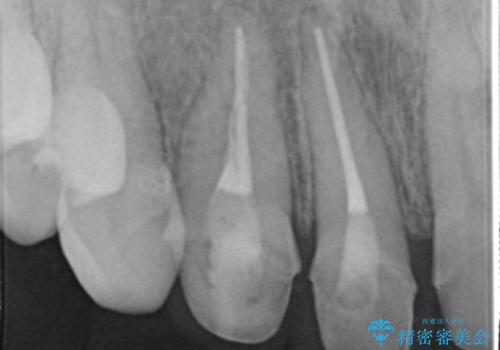

- 1週間ほど前に自転車で転倒して前歯をぶつけた後、歯の色が変わっていることが気になり受診された方です。診察の結果、失活及びエナメル質に多数の亀裂が認められたため、根管処置およびセラミッククラウンによる治療を行いました。元々右上2番目の歯の形が気になっていたとの事で、左右対称の形に近づけるように補綴しました。

左上1番目の歯は失活していませんでしたが、歯の表面に多数の亀裂が認められました。患者様のご希望により、前歯3本をまとめて補綴処置することとなりました。土台となる歯質の色が異なる状態でしたが、熟練した技工士さんの技術により3本とも同じ色味になるように仕上げていただきました。色味、形態ともに自然な被せ物に大変喜んでいただけました。